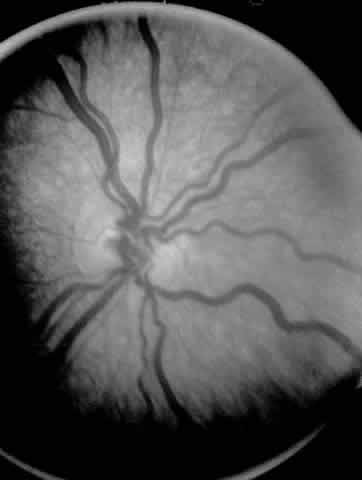

ROP accounts for a large number of retinal detachments in the pediatric population. The International Classification of Retinopathy of Prematurity helped greatly to improve communication about, and consequently treatment of, ROP. It describes affected eyes in terms of stage, zone, and absence or presence of plus disease18 (Figs. 1, 2, and 3). Screening of premature infants is an important feature in the care of ROP, which is perhaps the most significant and enduring finding of the Cryotherapy for Retinopathy of Prematurity Study (Cryo-ROP Study).19

Fig. 2. Standard zoning patterns of retinopathy of prematurity. Zone 1 is defined as a circle with a radius of two times the distance between the center of the optic nerve and the foveola. Zone 2 is a circle whose radius is from the center of the optic nerve to the nasal horizontal ora serrata. All the remaining area of retina is zone 3.

Fig. 3. Dilated and tortuous vessels in the posterior pole, which by definition is plus disease.